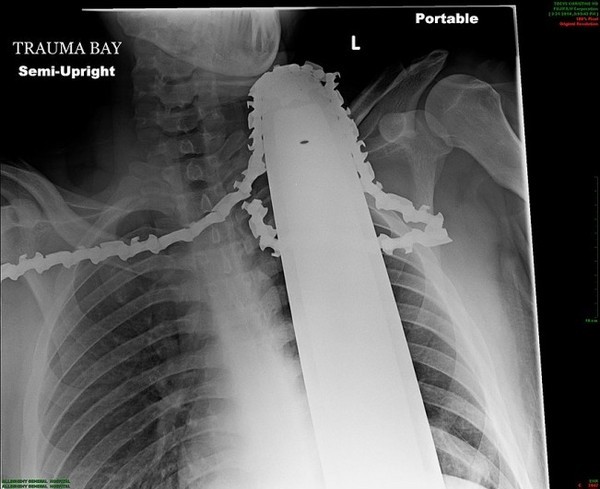

这张胸部透视片上可以看到这名患者詹姆斯・瓦伦丁(James Valentine)的脖子到胸腔位置有一个电锯的锯链。当时瓦伦丁正和同事们一同在伐木,突然电锯的链条断裂并反弹回来,切穿了瓦伦丁的胸腔,他被送往医院